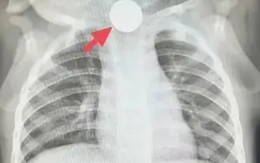

Bé trai 1 tuổi bỏ ăn cả tuần, nguyên nhân được phát hiện khiến bà nội phải thốt lên: “Đúng là lỗi của tôi”

Một bé 1 tuổi bỗng nhiên thay đổi tính nết, chán ăn suốt một tuần! Sau khi được bác sĩ ở Thượng Hải thăm khám, nguyên nhân được phát hiện khiến bà nội nhận ra là sơ suất của mình.